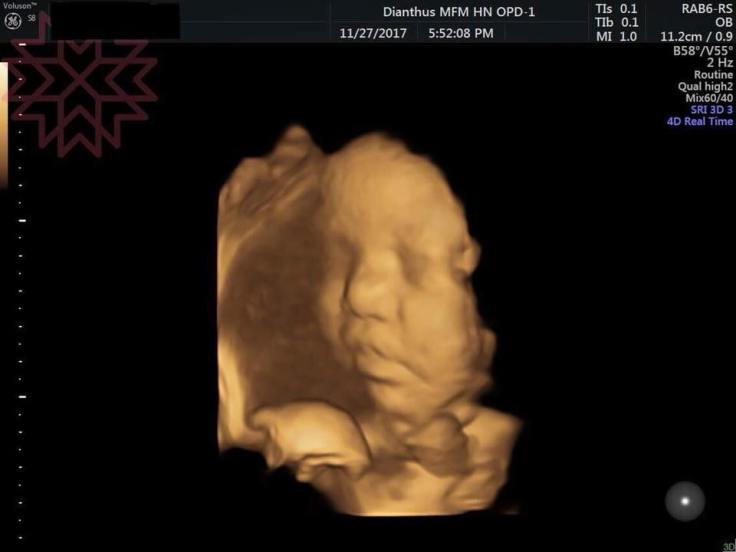

很多人會問我3D跟4D超音波的差別

直接看圖吧

用圖來說明最清楚了

有動態影像的就是4D

而把動態截取影像下來變成靜態圖片就是3D

多1D就是加上時間軸

傳統灰階影像就是2D

又叫做二維超音波